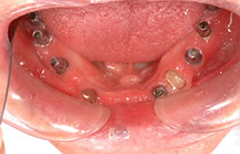

下顎の無歯顎に8本のインプラントを埋入して咬み合わせを作った症例

下顎全顎にインプラント埋入(8本)後、セラミックの歯を装着し、上顎は総義歯をいれた。

約7年経過後も問題はございません。